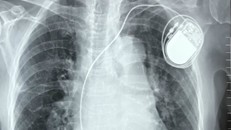

Sau khi các bác sỹ thăm khám, chụp chiếu, kết quả cho thấy khối u kích thước 10x6cm chiếm toàn bộ vú trái bệnh nhân, được chẩn đoán ung thư vú giai đoạn tiến triển.